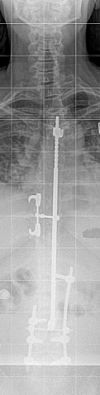

Case presentation: We report the case of a 46-year-old Caucasian woman who underwent surgery due to idiopathic scoliosis with a Harrington Instrumentation (T4 to L3) 30 years ago. During the operation she was infected with hepatitis C while receiving erythrocyte concentrates and has suffered from liver cirrhosis since then. She presented with a sudden pain in her lower back and paraesthesia in both her legs but no other neurological symptoms. A computed tomography scan showed a bilateral pedicle fracture of L3 and an additional compression fracture of L4. In the first session we performed a dorsal stabilization with massive intraoperative bleeding and a postoperative failure of liver synthesis. In a second session an additional ventral augmentation was done. After the second operation she developed a hepatorenal syndrome. Both operations left the patient in a very critical state which led to a prolonged stay in the intensive care and rehabilitation unit. At her 12-month follow-up visit, she was free of complaints.